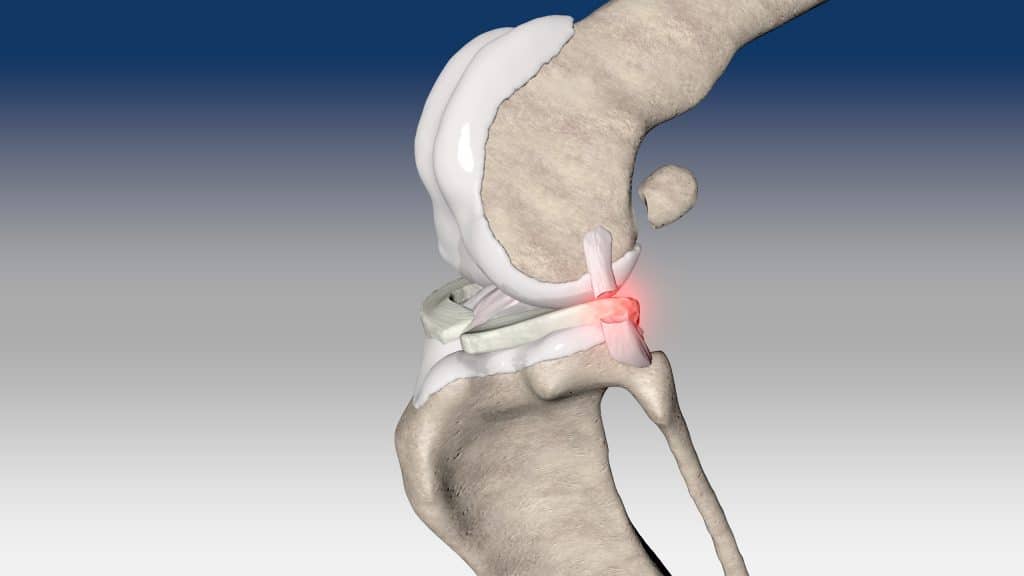

Izolované ruptury kaudálního zkříženého vazu jsou vzácné a existuje jen málo řešení.

NOVALIG® je syntetický vaz, který lze použít k rekonstrukci vazů a rychlému obnovení jejich fyziologických funkcí.

V případě zkřížených vazů umožňuje intraartikulární rekonstrukci v izometrických bodech připojení, čímž obnovuje biomechaniku kolene a všechny funkce natrženého vazu.

V případě více vazů kolene (kraniální, kaudální, kolaterální) je možné pomocí NOVALIG® anatomicky rekonstruovat každý vaz.